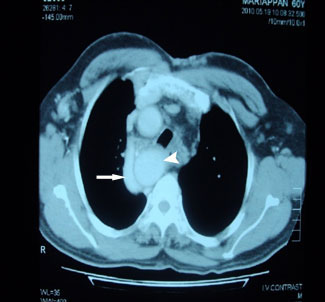

possibility of Idiopathic Fibrosing Mediastinitis. CT scan

chest shows fibrosis of mediastinum (black arrow) distended

azygos vein (white arrow), Right sided aorta (white arrow head) MRI chest